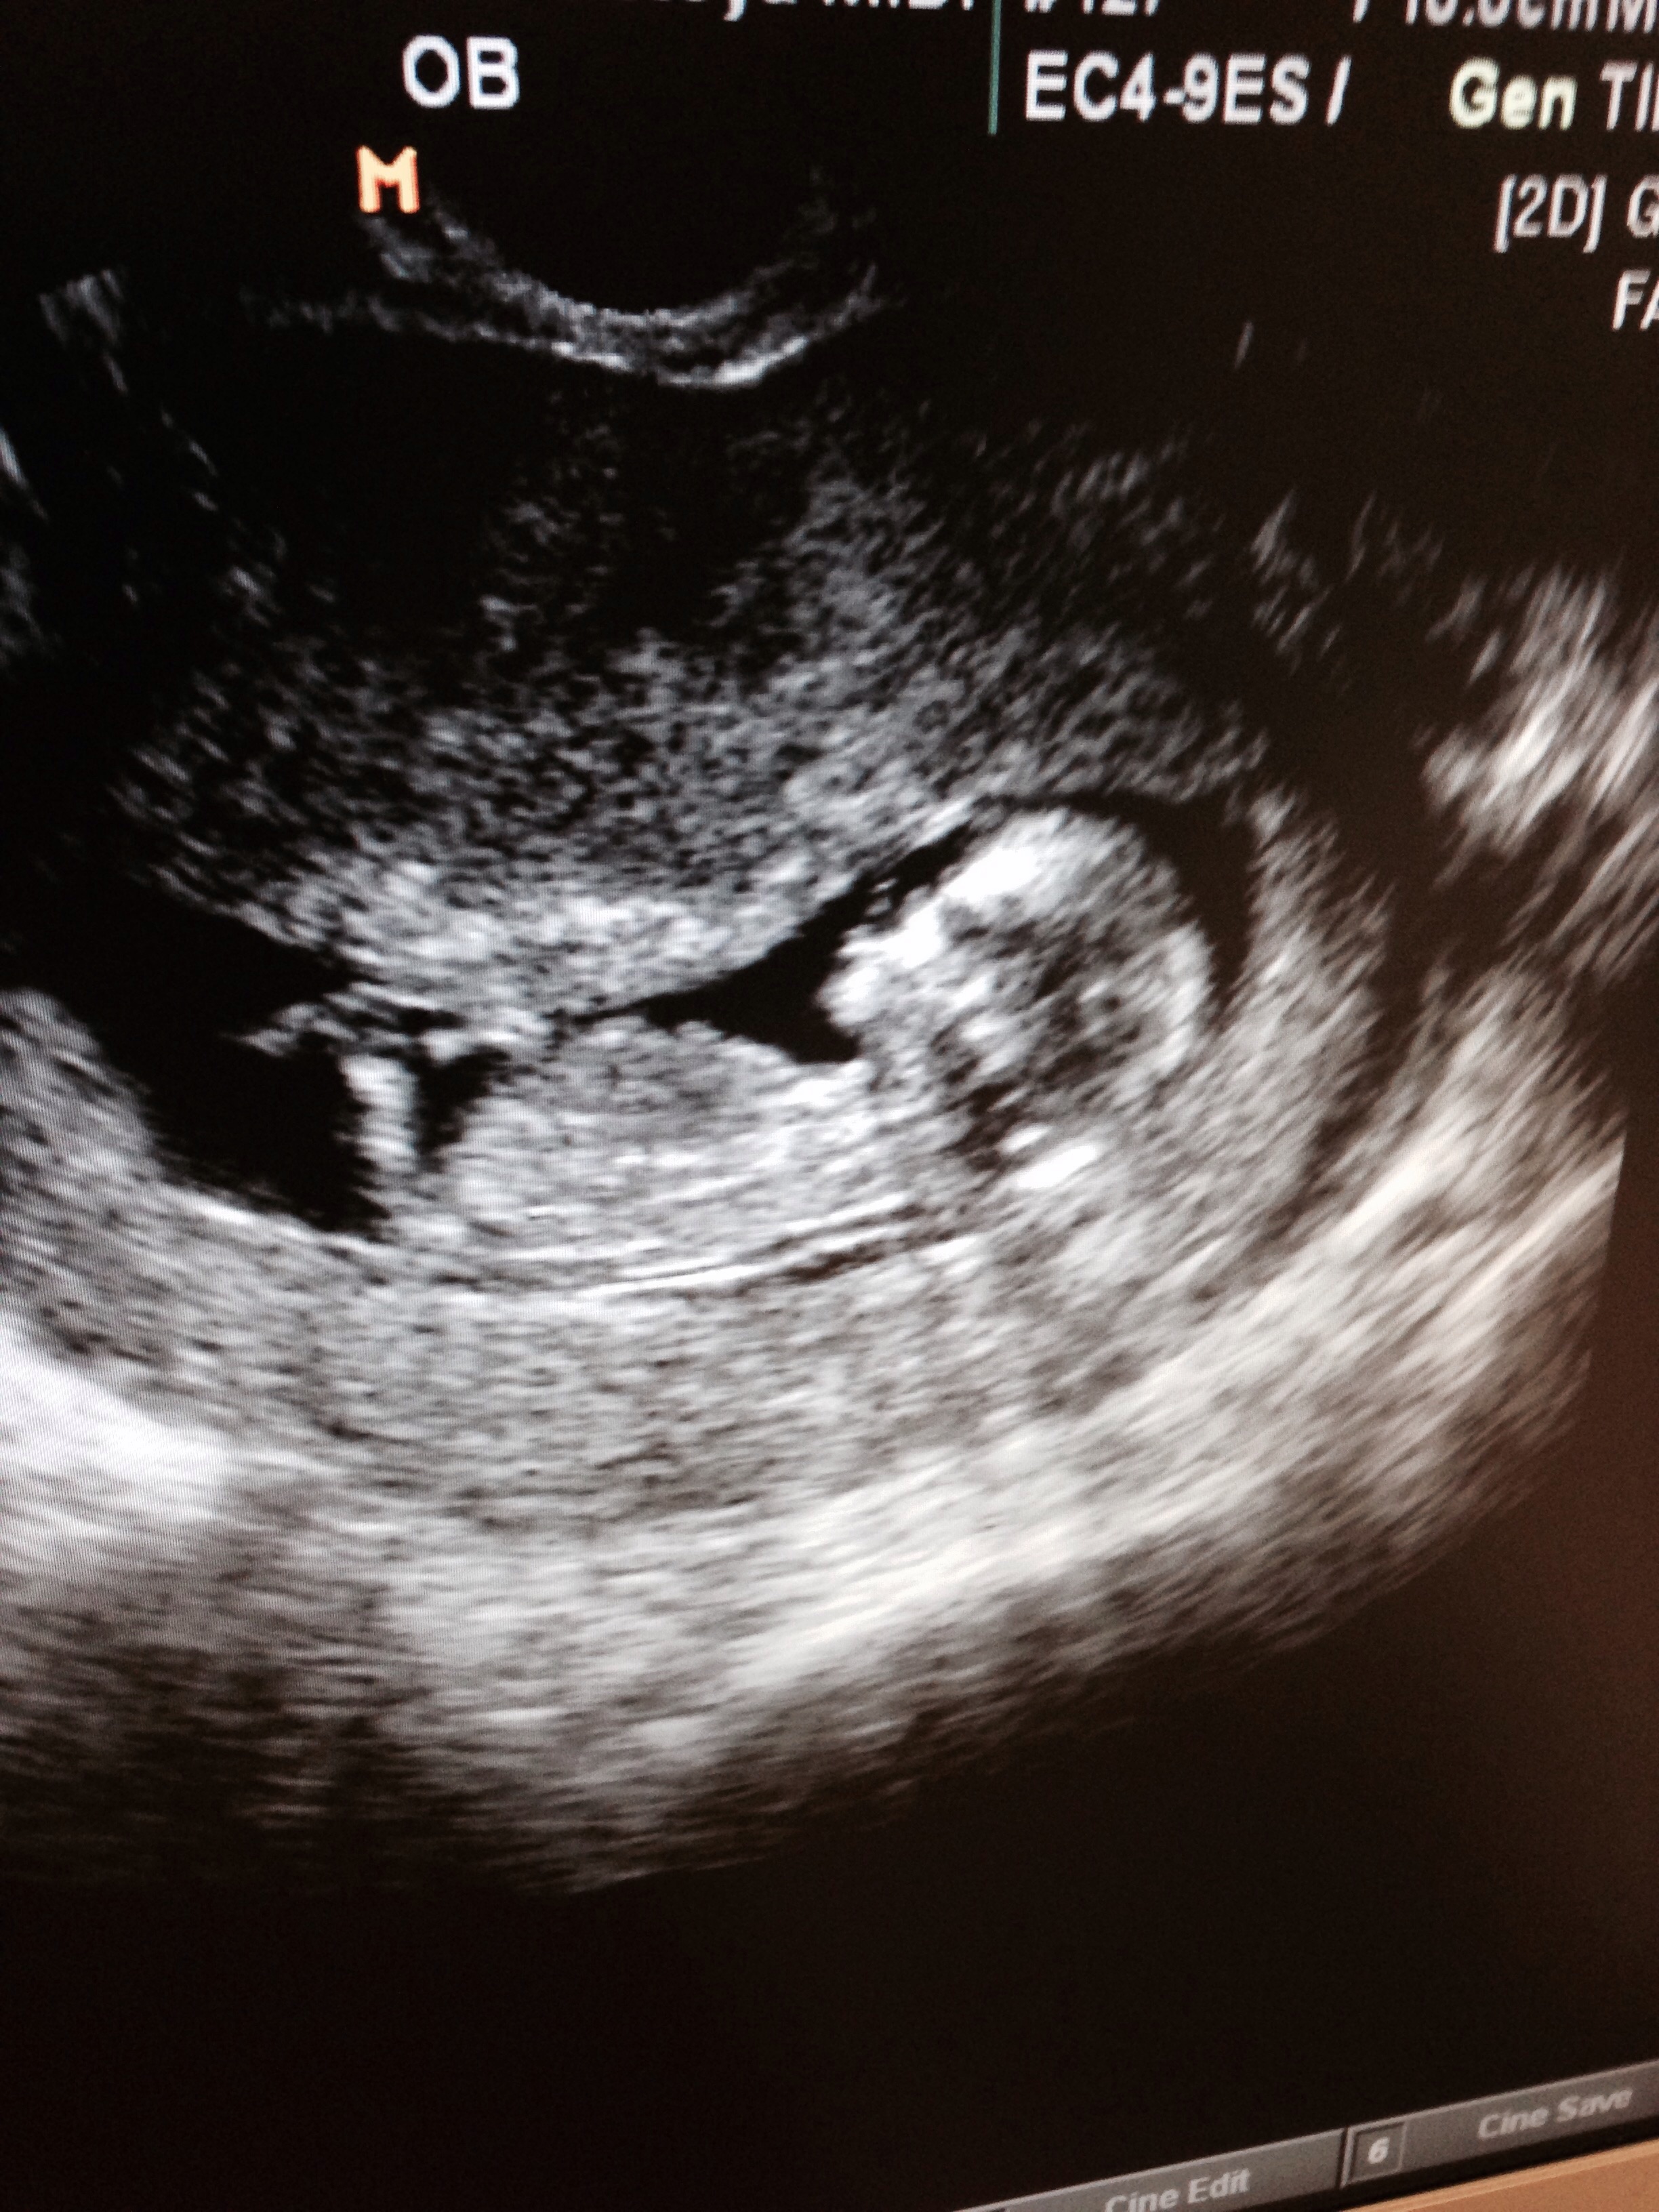

Oh I'm so excited to post! Had a mini scare over the weekend and went in for a super quick scan yesterday to make sure everything was ok! It was Great actually! Heard the little ones heartbeat for the 1st time - AMAZING. Here (s)he is at 10 weeks 6 days.